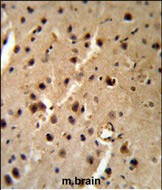

- PTHLH Antibody (Center) (Cat.#P30368) IHC analysis in formalin fixed and paraffin embedded mouse brain tissue followed by peroxidase conjugation of the secondary antibody and DAB staining. This data demonstrates the use of the PTHLH Antibody (Center) for immunohistochemistry. Clinical relevance has not been evaluated.